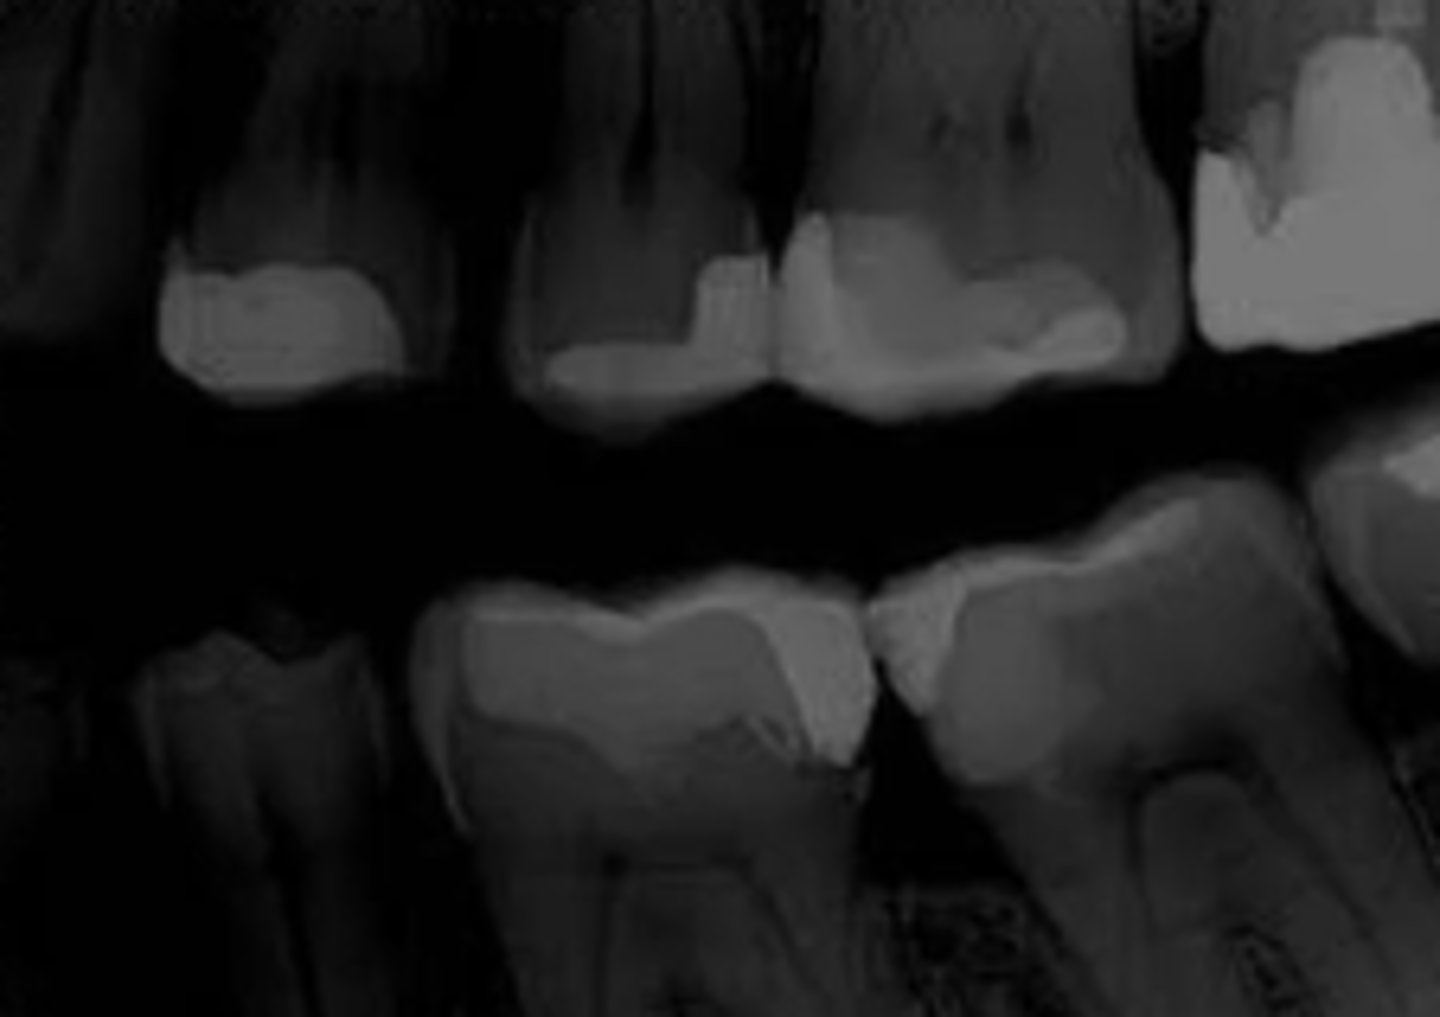

What error occurred here?

- Fixer time or temperature too low

- Radiograph opaque